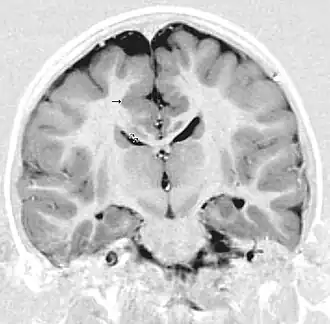

La polymicrogyrie est principalement une anomalie de l'organisation corticale des neurones probablement par un trouble de la migration des neurones à l'origine des dernières couches cellulaires du cortex cérébral : le cortex cérébral est plus épais avec de multiples circonvolutions.

Le diagnostic repose uniquement sur l'imagerie à résonance magnétique. La polymicrogyrie peut être isolée ou associée à d'autres anomalies : agénésie du corps calleux, schizencéphalie. Les diagnostics différentiels principaux sont la pachygyrie et la lissencéphalie.